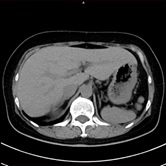

胸部CT画像 腹部CT画像

単純CT画像 造影CT画像 MPR画像